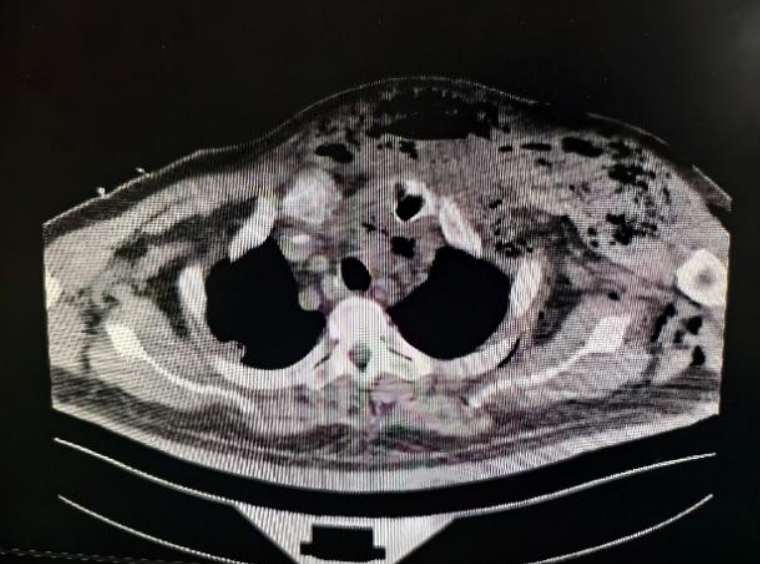

今年1月初,一名男性患者因突发前胸部、颈部大面积坏死性筋膜炎,合并凶险纵隔脓肿,紧急送入我院重症医学科监护治疗。

据了解,坏死性筋膜炎素有“食肉菌感染”之称,是进展极快、致死率极高的急性软组织坏死性感染,病菌会快速侵蚀皮下筋膜与肌肉组织;而纵隔脓肿紧邻心脏、大血管等核心器官,位置深、解剖复杂,感染极易扩散引发感染性休克、多器官衰竭,双重重症叠加,让患者的病情瞬间陷入绝境。

就在患者生命悬于一线之际,烧伤整形科主任金升元接到会诊通知,第一时间赶赴重症医学科。凭借多年深耕烧伤整形领域的临床经验和敏锐的病情判断力,金升元快速梳理病情、精准评估病灶范围,当即作出关键诊疗决策:需立即实施手术清创,阻断感染扩散,为患者争取生机。

时间就是生命,为避免病情进一步恶化,金升元迅速协调手术团队,高效完善术前各项准备工作,当晚便带领团队开展紧急手术。术中,团队精准剥离坏死组织、彻底清除脓肿病灶,层层推进、步步严谨,成功阻断感染蔓延,为患者守住了生命底线。